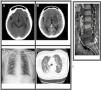

La tuberculosis es una enfermedad de gran prevalencia en países en vía de desarrollo, siendo su presentación pulmonar la más frecuente y de interés en salud pública. Sin embargo, existen diversas presentaciones clínicas inusuales que dificultan el diagnóstico oportuno por parte del clínico, lo cual representa todo un desafío médico y altas tasas de morbimortalidad. A continuación, se presenta el caso de una paciente femenina en su quinta década de vida con antecedentes de fístula de líquido cefalorraquídeo y osteomielitis lumbar, el cual progresa tempranamente a un caso grave de tuberculosis miliar asociada a mal de Pott y meningoencefalitis tuberculosa a pesar de no referir sintomatología respiratoria previa. Pese al manejo intrahospitalario recibido, terapia antibiótica y soporte ventilatorio, la paciente presentó deterioro hemodinámico con inestabilidad por lo que falleció el día cuatro de hospitalización.

Tuberculosis is a disease of great prevalence in developing countries, its pulmonary presentation being the most frequent and of interest in public health. However, there are various unusual clinical presentations that make timely diagnosis by the clinician difficult, which represents a medical challenge and high rates of morbidity and mortality. We present the case of a female patient in her fifth decade of life with a history of cerebrospinal fluid fistula and lumbar osteomyelitis, which progressed early to severe miliary tuberculosis associated with Pott's disease and tuberculous meningoencephalitis despite not reporting previous respiratory symptoms. Despite the in-hospital management received, antibiotic therapy and ventilatory support, the patient had haemodynamic deterioration with instability, from which she died on day four of hospitalization.